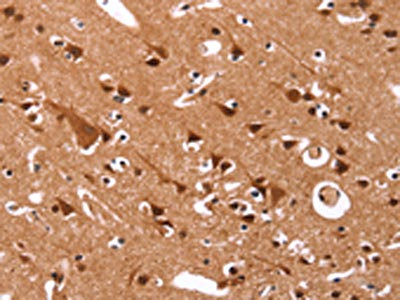

The image on the left is immunohistochemistry of paraffin-embedded Human brain tissue using CSB-PA975999(CCND3 Antibody) at dilution 1/40, on the right is treated with synthetic peptide. (Original magnification: ×200)